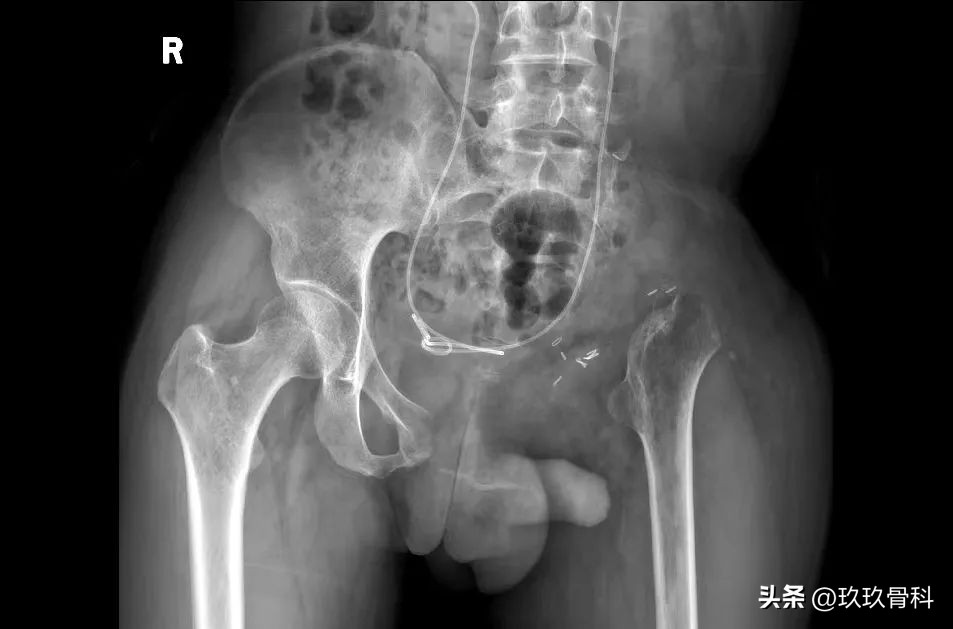

术前影像

2022-08-19 骨盆CT:左侧骨盆术后改变。